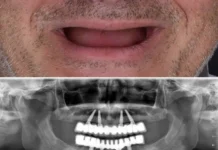

Affordable All-on-4 Dental Implants in Brisbane: Your Comprehensive Guide

Introduction: Are you considering All-on-4 dental implants but worried about the cost? Sandgate Bayside Dental is here to make this transformative procedure accessible to...